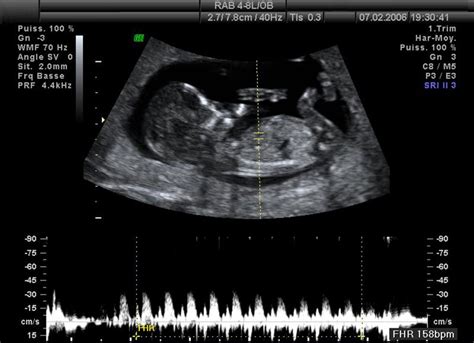

Každá budúca mamička s očakávaním pozoruje akrobatické kúsky svojho drobca na ultrazvuku, no zvláštne je, že ich vôbec necíti. Kedy, v ktorom týždni, mesiaci či trimestri môžete očakávať prvé kopance? Pravdou je, že práve prvý trimester je pre vývoj bábätka najdôležitejší, pretože sa vyvíjajú všetky životné systémy a orgány.

Ten rapídny pohyb na UTZ je kľúčový aj pre vývoj svalového a kostrového systému - dieťa naberá na sile, postupne začne priberať a teda sa spoločne priblížite k momentu, kedy jeho pohyb prvýkrát pocítite: k 20. týždňu tehotenstva, 5. mesiacu, II. trimestru.

No spomínané rapídne pohyby embrya v maternici začínajú oveľa skôr - hýbať rukami a nohami začína od 9. týždňa, od 11. pohybuje hlavičkou zo strany na stranu. Mnohé mamičky sa s veľkými očakávaniami tešia na prvý veľký ultrazvuk, ktorý sa vykonáva v období medzi 11. a 13. týždňom tehotenstva, a rovnako druhý veľký ultrazvuk medzi 19. a 22. týždňom tehotenstva.

„Niektoré viacrodičky môžu cítiť pohyby už od 17. týždňa gravidity,“ doplnil gynekológ. A ako odpovedá na otázku, ako teda prvé pohyby rozpoznať? „Keď bude žena cítiť pohyby, tak to bude vedieť jasne, že je to ono. Je to niečo, čo dovtedy nezažila a určite bude vedieť, že to nie je napríklad zvýšený pohyb čriev… Okolo 20. týždňa sa robí morfologický ultrazvuk, tzv. II. skríning, ktorý jasne zadefinuje, či daný vývoj plodu aj v prípade, že žena necíti pohyby, je správny.“ Závisieť však bude aj od napríklad umiestnenia placenty v maternici (ženy, ktoré ju majú na brušnej stene, môžu pohyby registrovať neskôr a je to trochu ťažšie) či množstva plodovej vody.

- 12. tt, 3. mesiac, II. trimester: Dieťatko sa v maternici rapídne hýbe, pohyby vidíte na UTZ, ale ešte necítite